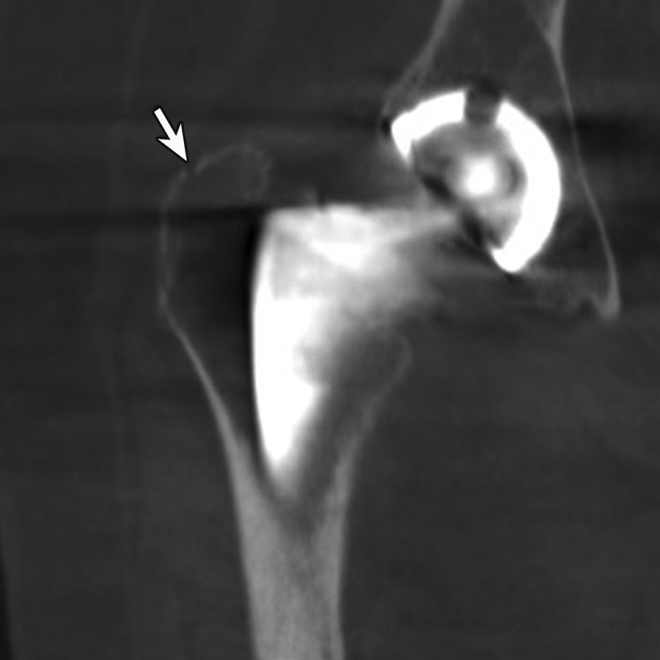

While periprosthetic fractures may occur acutely or chronically following fracture fixation or arthroplasty, CT may be more beneficial in the chronic setting to accurately assess the exact extension of the fracture and residual bone volume, which may be obscured by overlying surgical hardware (Figure 8) (Ohashi, 2009). Further, CT may be helpful to better assess multiple overlapping screws or complex hardware before surgical intervention. Cross-sectional imaging with CT or MRI may also be useful for the assessment of incomplete or stress fractures resulting in chronic post-operative pain.

Periprosthetic Fracture. (A) Coronal multiplanar reformation and (B) axial CT image of the right hip demonstrate radiographically occult non-displaced periprosthetic fracture involving the greater trochanter (arrow)